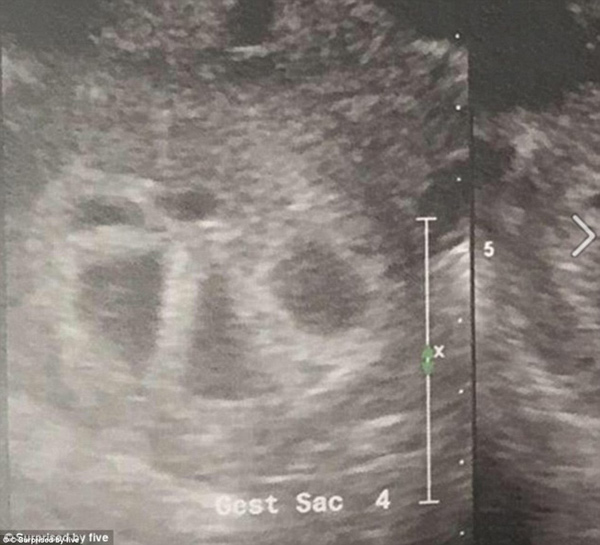

When she asked to use another sonogram machine so she could have a clearer view of the babies, her world was turned upside-down when the doctor found five separate heart beats.

Mrs Tucci asked to take a second sonogram to see her babies better and doctors were shocked to find out that instead of two heartbeats, there were five.